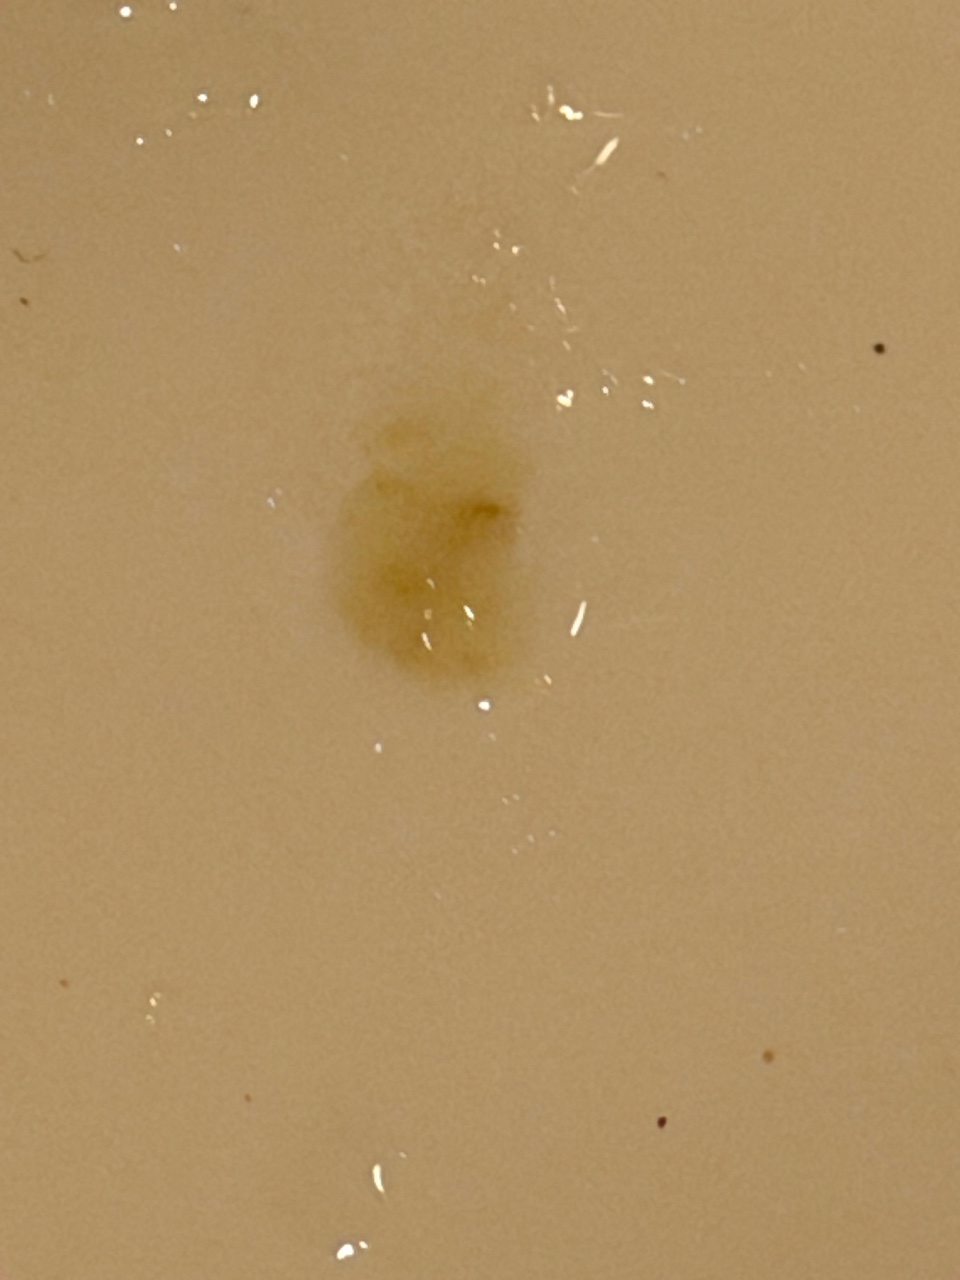

Здравствуйте, 2-3 недели назад начался кашель с мокротой желто-зеленого цвета. Чаще утром но в течении дня тоже бывает. Стаж курения 10 лет. Других симптомов (кроме паники) не наблюдаю. К врачу терапевту попаду только через несколько дней, так что свежих анализов на руках нет. Есть анализы 3 месячной давности, анализ крови и рентген груди. Никаких отклонений в заключениях нет. Недавно была мокрота с кровяными прожилками, фото прилагаю. Подскажите, что этом может быть в перспективе и какие действия помимо отказа от курения можно предпринять. Заранее спасибо за ответ